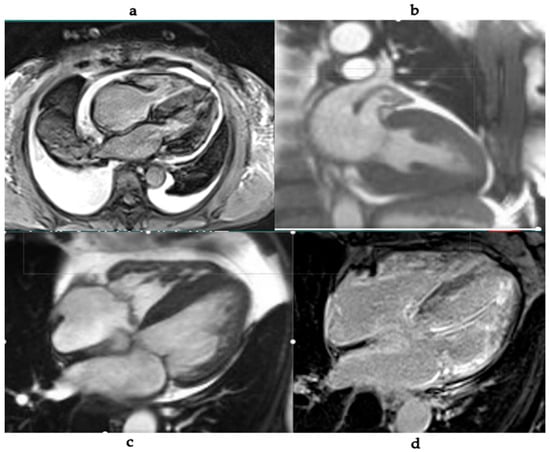

Multimodality Imaging in Cardiac Amyloidosis

by Mayuresh Chaudhari and Mahi Lakshmi Ashwath

Cardiac amyloidosis is an underdiagnosed cause of heart failure characterized by extracellular deposition of misfolded proteins. Advances in non-invasive imaging, including echocardiography, cardiac magnetic resonance imaging (CMR), and radionuclide imaging, have significantly enhanced the diagnostic accuracy and monitoring of cardiac amyloidosis. This review [...] Read more.

Cardiac amyloidosis is an underdiagnosed cause of heart failure characterized by extracellular deposition of misfolded proteins. Advances in non-invasive imaging, including echocardiography, cardiac magnetic resonance imaging (CMR), and radionuclide imaging, have significantly enhanced the diagnostic accuracy and monitoring of cardiac amyloidosis. This review explores the role of each modality, their individual strengths, and current consensus recommendations. Emphasis is placed on the integration of multimodal imaging to guide diagnosis, prognosis, and therapeutic decisions in both AL and ATTR amyloidosis. Full article

Show Figures

Figure 1